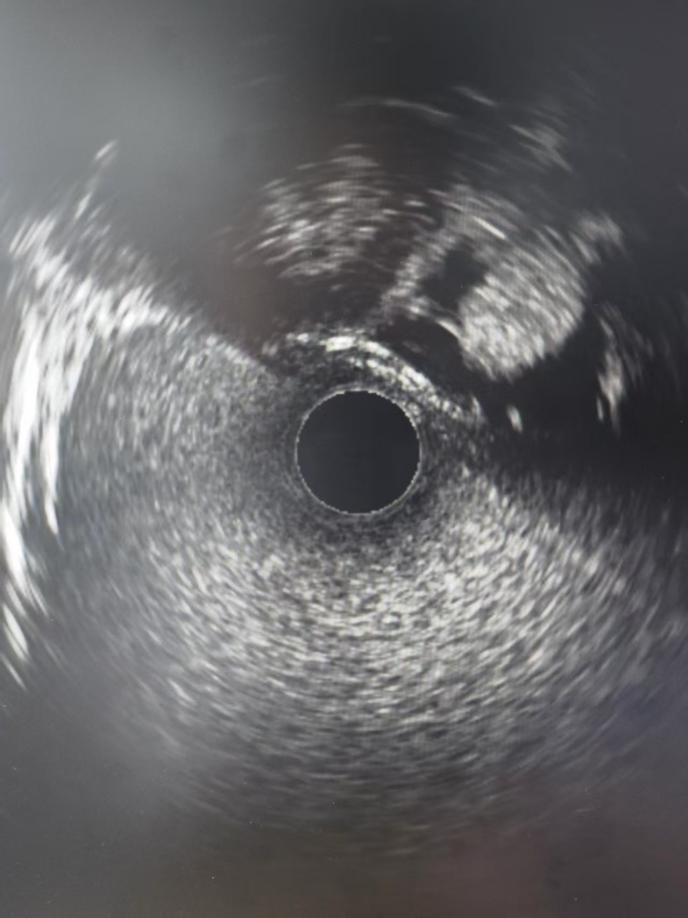

神经内二科团队分析讨论后,为患者实施了静脉窦造影术+测压+血管内超声检查。造影提示右侧横-乙状窦交界区局限性狭窄,测压提示狭窄近-远端压力差3 mmHg,血管内超声探及静脉窦内多个类圆形凸起,提示内源性狭窄,考虑蛛网膜颗粒所致局限性狭窄。

特发性颅内高压(IIH)的病理生理学可能受到脑窦内结构变化的影响,而特发性颅高压伴静脉窦狭窄包括内源性和外源性两种形态类型。相比于其他检测手段,血管内超声能够提供更真实、准确的静脉窦腔内成分描述,有助于更深入了解特发性颅内高压特点,为该类患者静脉窦狭窄的血管内介入治疗提供有价值的支持。血管内超声(IVUS)可观察到各种类型狭窄,并进行描述性分析,显示了血管内超声(IVUS)在鉴别内、外狭窄类型,内源性狭窄腔内成分和壁内成分方面的潜力。

静脉窦内行血管超声检查为五楼自拍